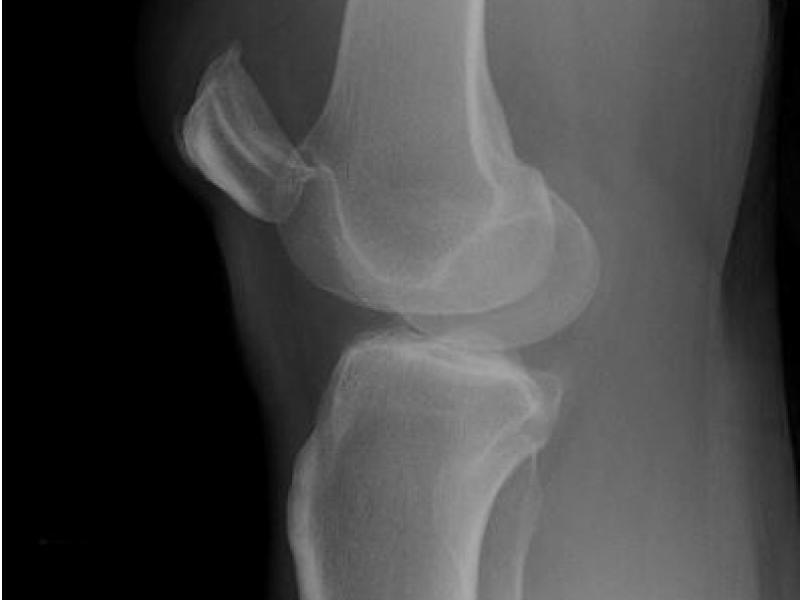

What's the Diagnosis? By Dr. Erica Schramm

A 40 year old female presents with right knee pain after she